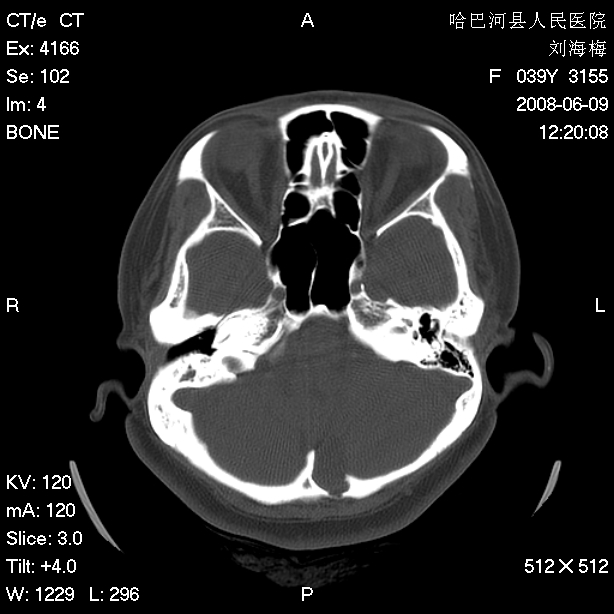

标题: CT13909:F39Y,头痛1年 [打印本页]

标题: CT13909:F39Y,头痛1年

头痛1年

枕骨蛛网膜颗粒压迹。

嗜酸性肉芽肿?骨髓瘤?不像蛛网膜颗粒压迹,太大了,并且有占位效应。

枕骨胆脂瘤

支持枕骨胆脂瘤可能性最大。右侧乳突部密度增高,建议薄扫。

枕骨皮样囊肿。

也称囊性畸胎瘤,含有中外胚层组织成分,囊壁厚,内含大量油脂、表皮、真皮及其中毛囊、皮脂腺汗腺等,常与皮肤之间有一窦道相连,也可闭合成纤维条索等。